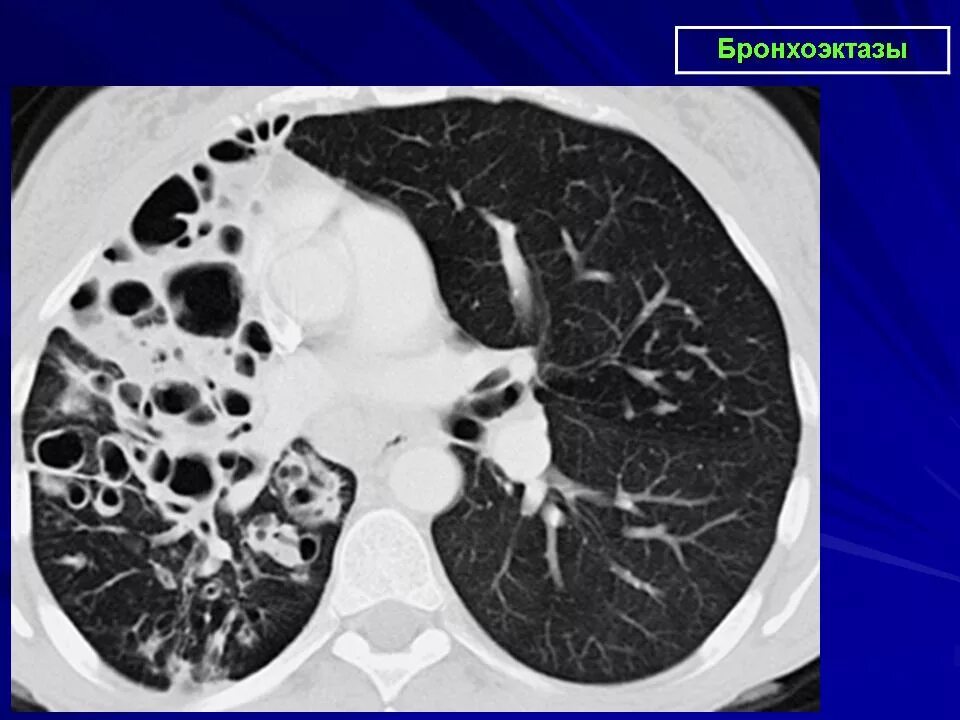

Заболевание кт